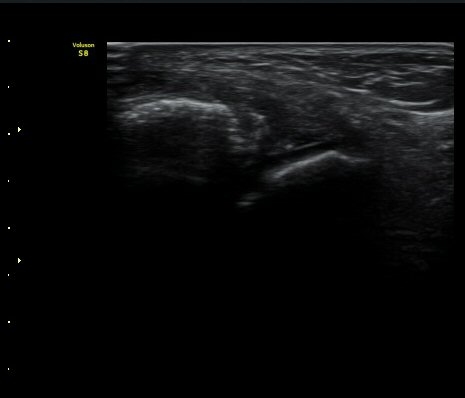

Àü°Å°ñºñ°ñÀδë Á¾´Ü¸é°Ë»ç»ó Àδë ÀδëÀÇ Àú¿¡ÄÚ ºÎÁ¾°ú ºñ°ñ

ºÎÂøºÎ ¹Ì¼¼ °ß¿­°ñÀýÀÌ °üÂûµÈ´Ù(±×¸² 3, 4).

3ÁÖ ÈÄ ÃßÀû°Ë»ç»ó °üÀý³» ºÎÁ¾ÀÌ ¼Ò½ÇµÇ°í(±×¸² 4). Àü°Å°ñºñ°ñÀδëÀÇ Àú¿¡ÄÚ ºÎÁ¾ÀÌ

°¨¼ÒÇÏ°í °ß¿­°ñÀý °ñÆíÀº ºñ°ñ °¡±îÀÌ À§Ä¡Çϰí ÀÖ´Ù(±×¸² 5, 6).

ÃÊÀ½ÆÄ Åõ½ÃÇÏ ºÎÇϰ˻翡¼­ ºñ°ñ°ú ÀδëºÎÂøºÎ¿Í  ºñ°ñ°ú °Å°ñ»çÀ̰¡ ¹ú¾îÁöÁö ¾Ê´Â´Ù

(樨毢 2).